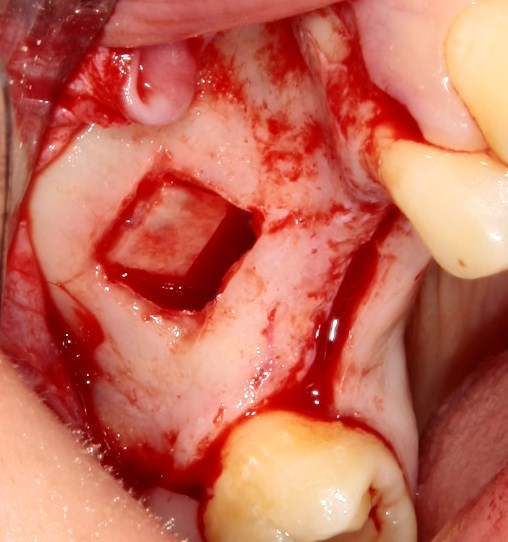

Нюансы начинаются с обработки принимающего ложа. Да-да, уважаемые друзья, одна из причин некроза блоков, их чрезмерной атрофии и прочих проблем — в отсутствии обработки принимающего ложа. Некоторые делают дырки, но правильнее и эффективнее поступить так:

то есть, просто снять слой кортикальной пластинки с участка, к которому будет фиксироваться костный блок. Почему? Читайте здесь>>.